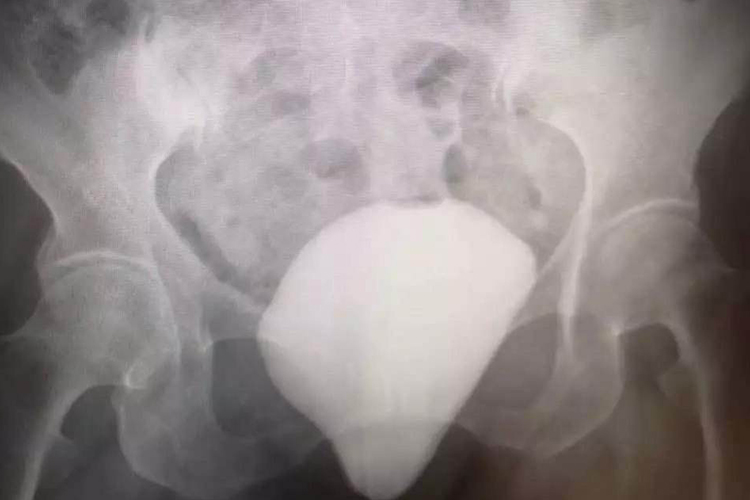

膀胱膨出属于前盆腔脏器膨出,是指膀胱向阴道前壁的膨出。多见于中老年妇女、多产妇。

根据阴道前壁脱垂情况,可将膀胱膨出分为三度,以评价疾病的严重程度。

根据阴道前壁脱垂情况可进行膀胱膨出的分度,以评价疾病的严重程度,可分为三度,轻者无症状,或有轻度下坠感、腰酸,重者可伴有排尿困难。

Ⅲ度

阴道前壁全部突出于阴道外口。